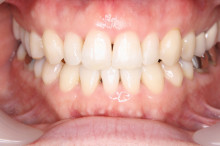

お口を拝見すると、前歯3本ほど 反対に噛んでいます。

原因は上あごに比べ下あごが大きいためと思われます。

下のあごを小さくするには外科手術が必要です。

患者さんとお話した結果、

今回は下の前歯を1本だけ抜いて、抜いた隙間を埋めることで

「下の歯並びを上の歯並びの内側に入れる」治療を行う

ことにしました。